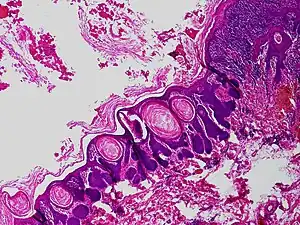

Trichofolliculoma

Trichofolliculoma is a cutaneous condition characterized by a benign, highly structured tumor of the pilosebaceous unit.[1][2] Trichofolliculoma is a rare tumor of the eyelid. It can be suspected by the “cotton bag sign”[3]